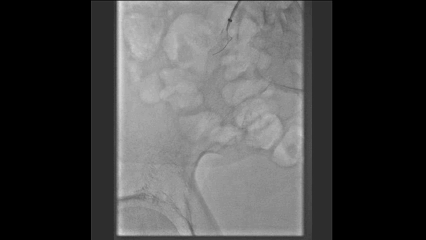

股总动脉斑块切除

使用TurboHawk Plus系统,于12、3、6点方向切除,因斑块硬在1点方向补切一刀(共四刀), 未放置远端保护伞。

药物球囊应用

切除后造影显示管腔获得良好,使用6-4药物球囊进行后扩张。